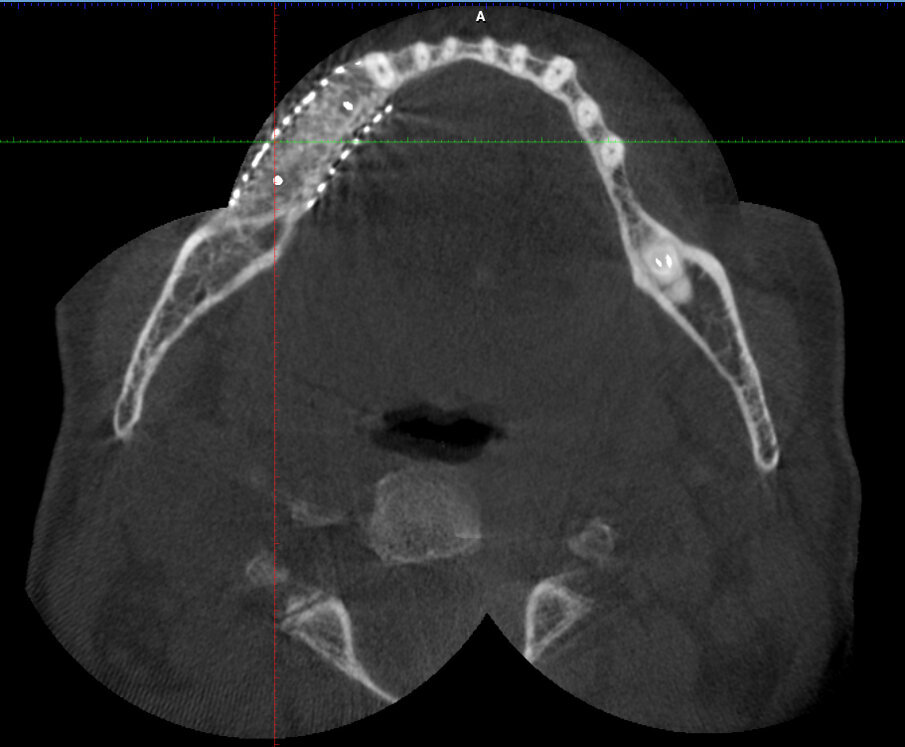

Figg. 1a-1c_Foto clinica e sezioni di CBCT iniziali in cui si evidenzia l’edentulia distale a elemento 4.3 con atrofia orizzontale estremamente accentuata e lieve atrofia verticale.